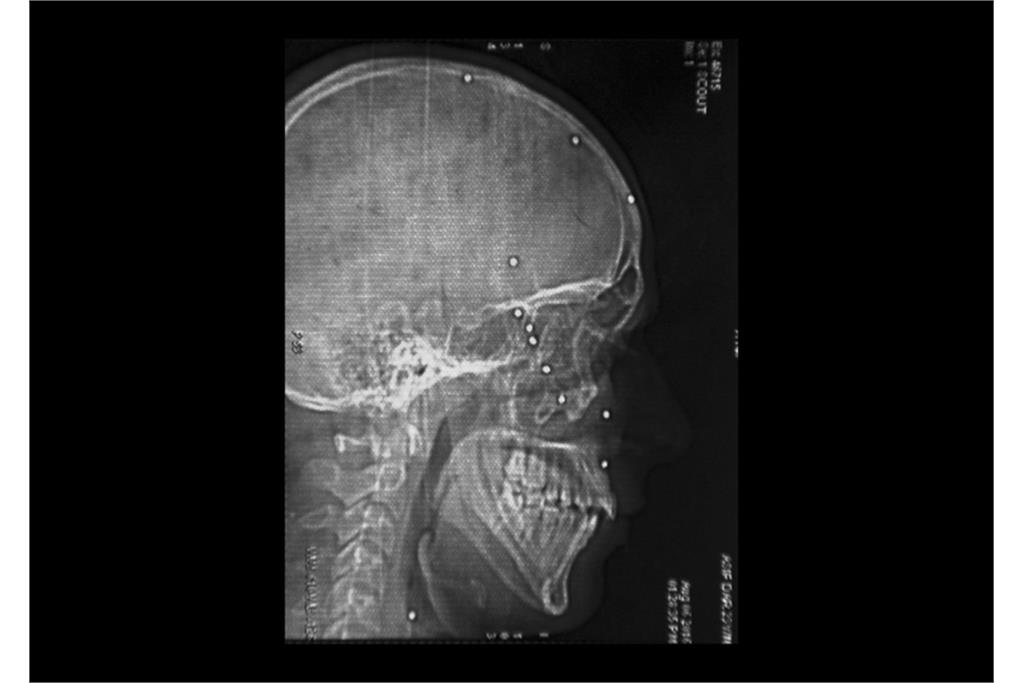

«دره‌ سایه‌ها» مجموعه‌ای از عکس‌ها و اسناد پزشکی در زمینه نقض سیستماتیک حقوق مردمان کشمیر و اعمال شدید‌ترین خشونت‌های دولتی در سرکوب آنها است و نشان دهنده سایه‌ سیاهی که بر دره‌ کشمیر افتاده است و مردمانی که از درون شکسته‌اند. هم‌نشینی بیرون(عکس‌های عادی) و درون (عکس‌های اشعه ایکس)‌ از افراد، تلنگر این فاجعه بر بیننده را دوچندان می‌کند.گویی درد پنهان و آشکار آن‌ها در تاریکی فرو می‌رود و از آن‌ها جز سایه‌ درد و نقطه‌های روشن ترکش‌های داخل بدنشان در عکس‌های اشعه ایکس چیزی باقی نمی‌ماند.